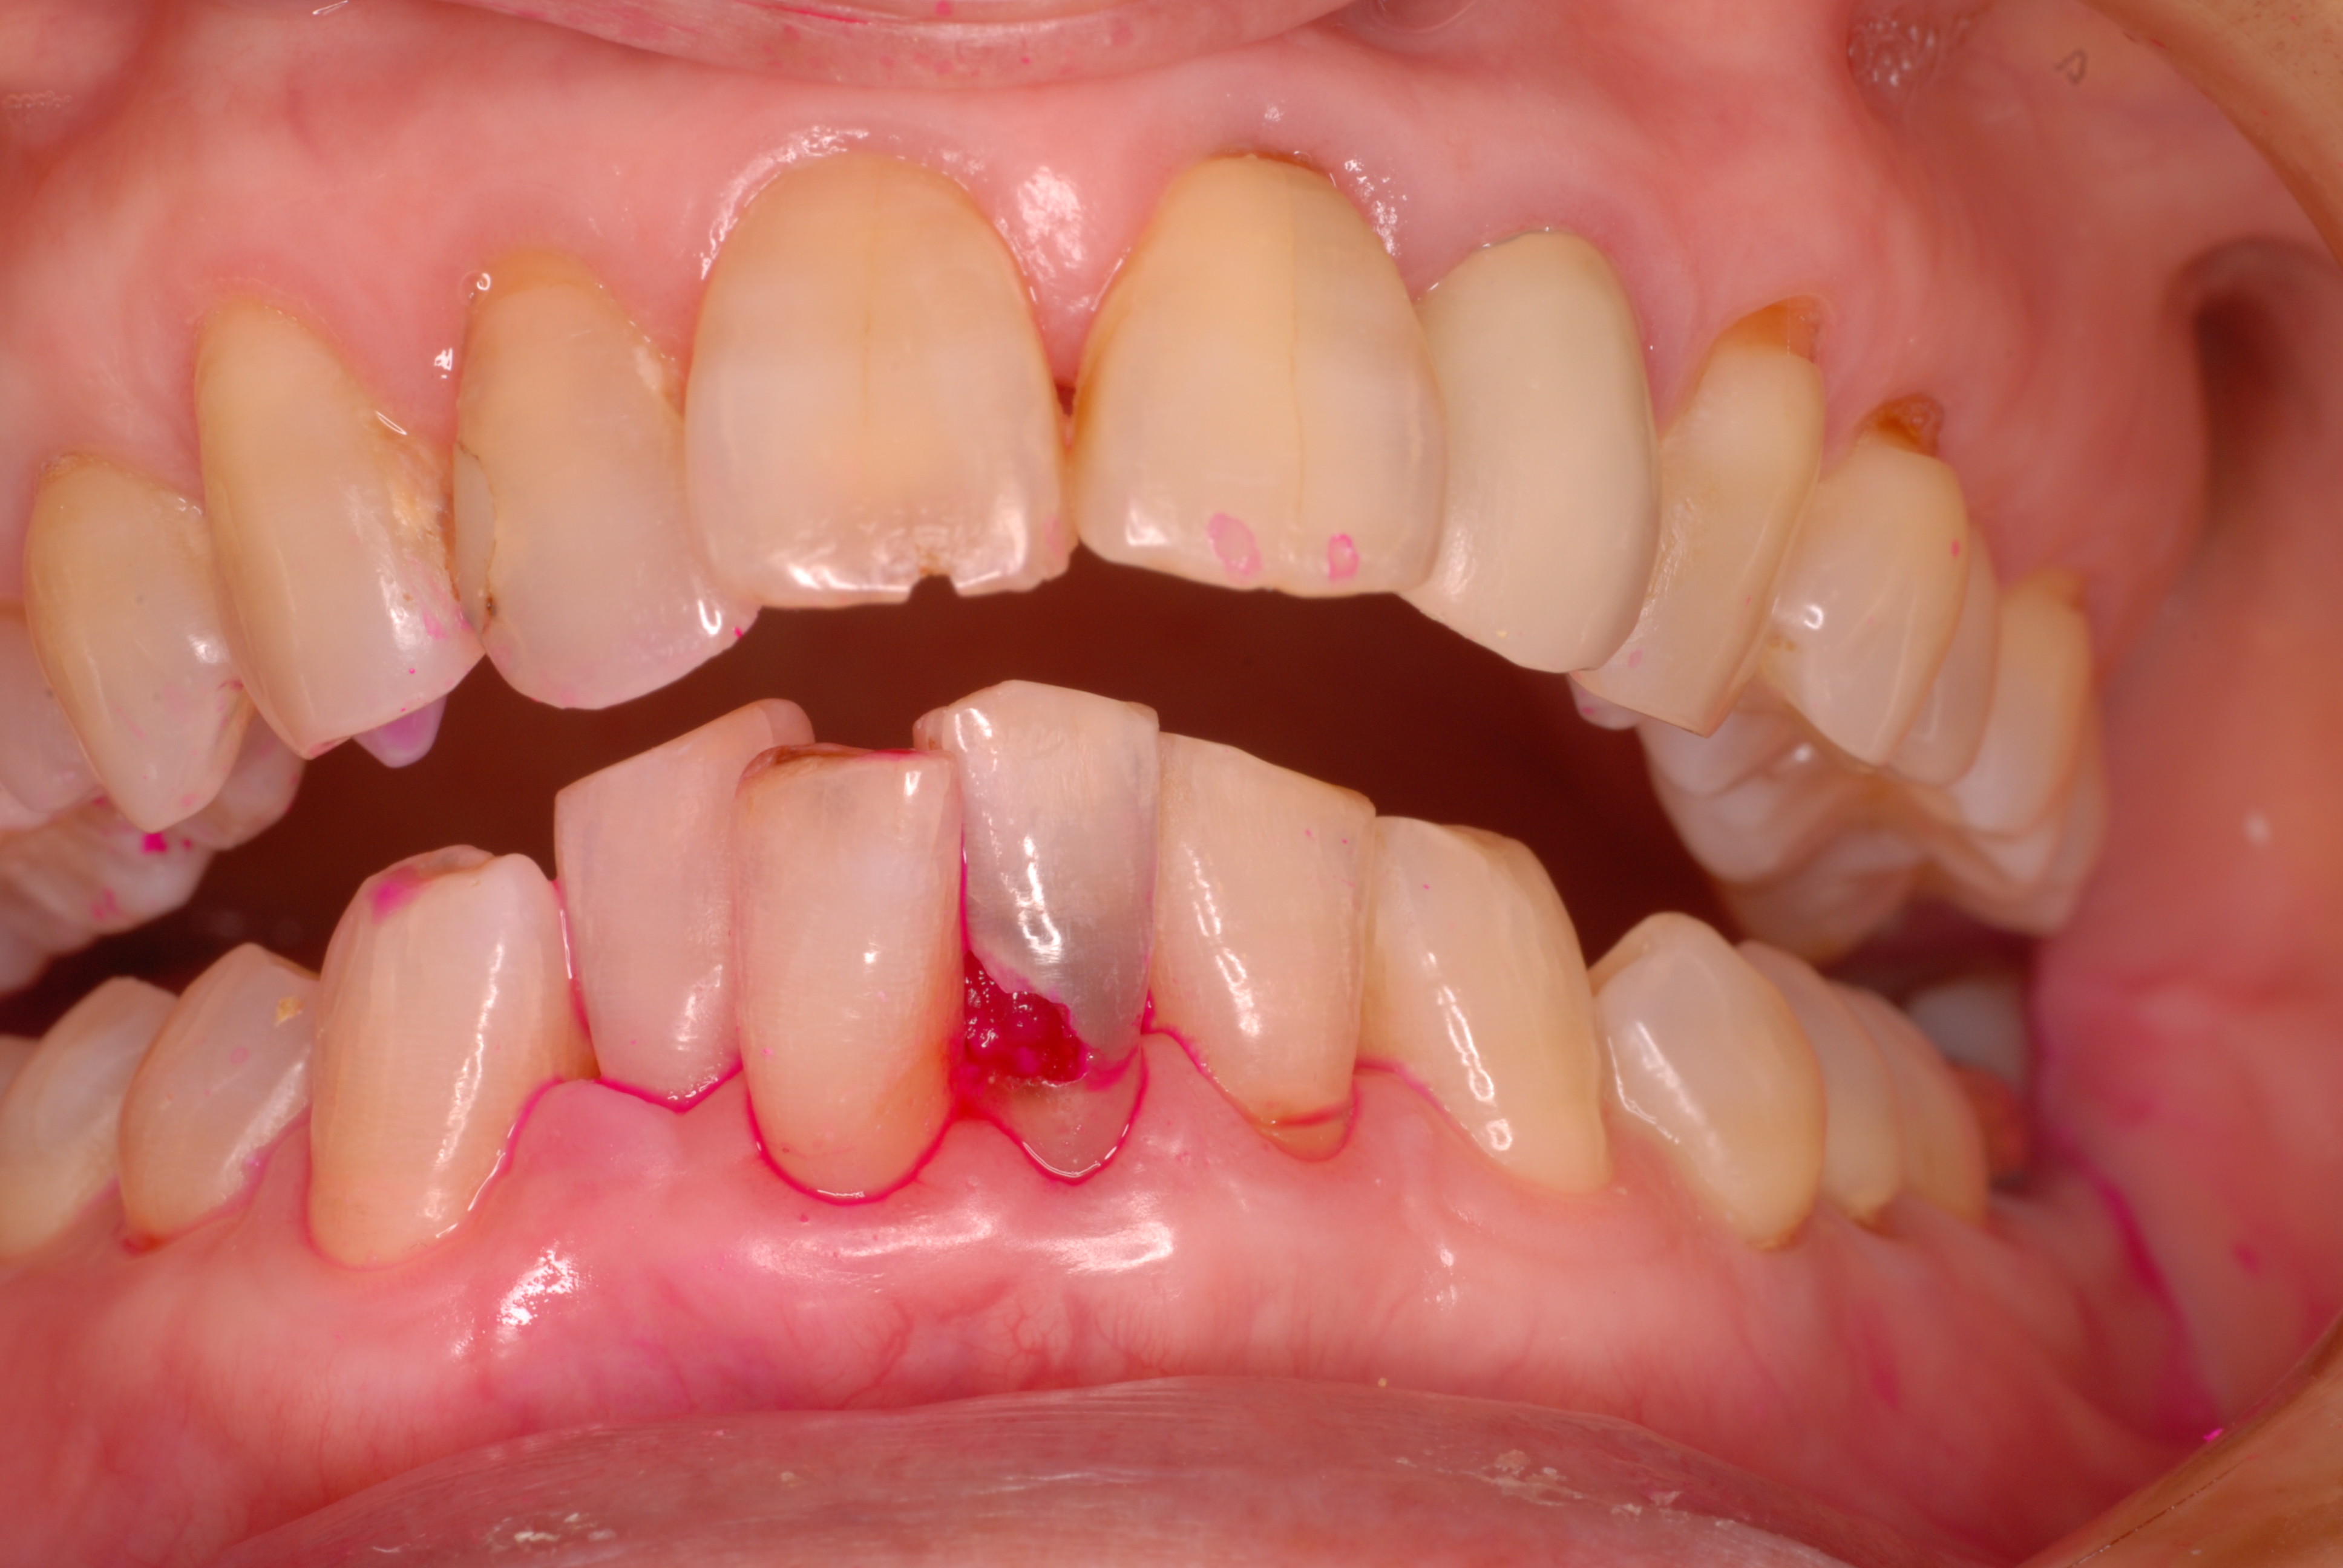

今度は下の歯が酷く折れそうでした。赤い色は虫歯菌の検知液です。

染まった所がばい菌の塊です。右上の真ん中の歯は虫歯もひどく神経を取った歯です。隣は何回も注意していたのですが、約束を守らず治療途中で硬いものを噛んだ為に折れて差し歯になったものです。

DSC_0004

DSC_0005